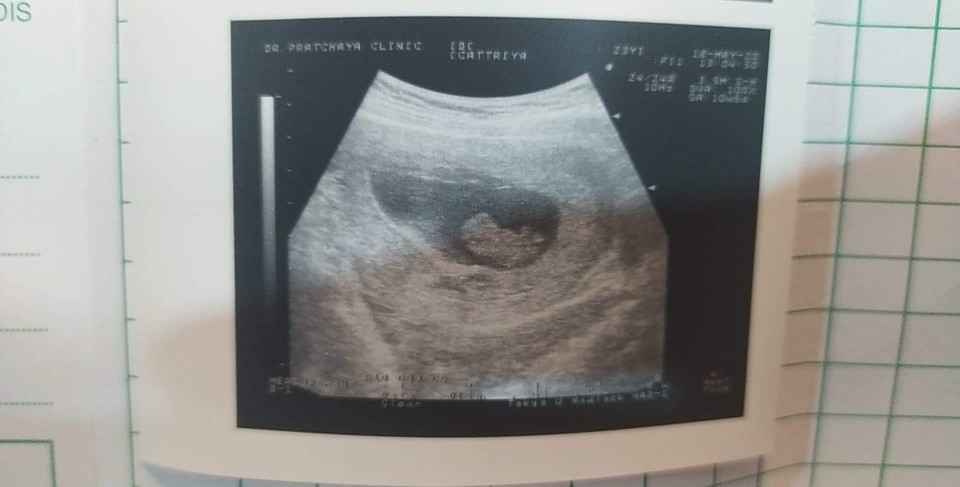

กำหนด24ธันวาจ้า😊